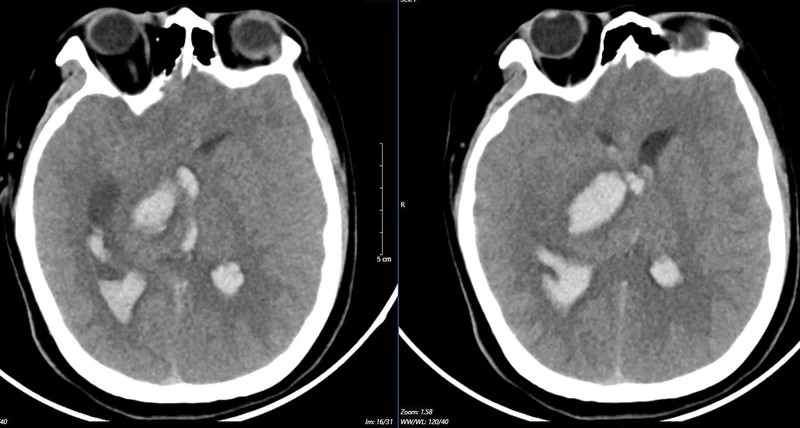

Hình ảnh chụp MSCT mạch não: Chảy máu não thuỳ đỉnh phải, chảy máu não thất do vỡ AVM ( điểm Spetzler Martin 2 điểm) của bệnh nhân nữ, 29 tuổi. |

Nữ bệnh nhân 29 tuổi, tiền sử khoẻ mạnh. Bệnh nhân đến viện vì đột ngột đau đầu, tê tay, nôn nhiều vật vã. Tại bệnh viện tỉnh, bệnh nhân được chẩn đoán chảy máu não, các bác sĩ đã đặt ống nội khí quản thở máy rồi chuyển tuyến lên Trung tâm Đột quỵ, Bệnh viện Bạch Mai trong tình trạng ý thức hôn mê, Glasgow 6 điểm, thở máy, đồng tử bên phải giãn 4mm, tụt huyết áp, duy trì vận mạch.

Kết quả chụp MSCT mạch não cho thấy chảy máu não thuỳ đỉnh phải, chảy máu não thất do vỡ AVM ( điểm Spetzler Martin 2 điểm). Bệnh nhân đã được phẫu thuật lấy máu tụ và khối dị dạng. Tuy được điều trị tích cực nhưng di chứng để lại vô cùng nặng nề. Sau một tháng điều trị, bệnh nhân chưa nhận thức được, liệt hoàn toàn nửa người trái…